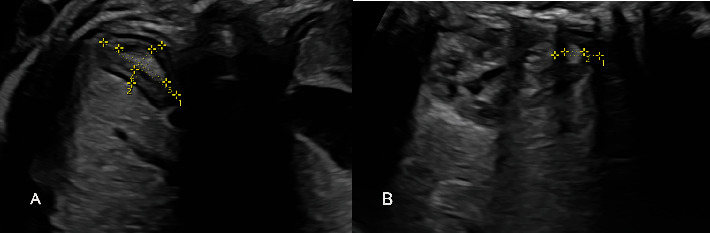

背景:生长受限(FGR)胎儿的子宫胎盘功能不全导致长期缺氧和应激,主要影响肾上腺。然而,其影响机制仍不清楚。研究目的本研究旨在比较 FGR 胎儿和发育正常胎儿的肾上腺动脉多普勒指数和肾上腺大小。材料和方法:于 2023 年 2 月至 12 月进行了一项多中心横断面研究。我们比较了 34 例 FGR 和 34 例发育正常婴儿的肾上腺下动脉(IAA)多普勒指数和肾上腺体积。结果显示FGR组的IAA峰值收缩速度(PSV)为14.9 ± 2.9 cm/s,而正常组为13.5 ± 2.0 cm/s,平均相差1.4 cm/s(95%置信区间[CI]:0.27-2.65;P值=0.017)。各组间的 IAA 脉动指数 (PI)、阻力指数 (RI) 或收缩/舒张 (S/D) 均无明显差异,P 值分别为 0.438、0.441 和 0.658。FGR组校正后的整个肾上腺体积和校正后的新皮质体积明显更大,P值分别为0.031和0.020。结论FGR胎儿的IAA PSV增加,校正后的整个肾上腺和新皮质体积增大,表明肾上腺对宫内慢性应激有明显的适应性。

Background: Uteroplacental insufficiency in fetuses with growth restriction (FGR) leads to chronic hypoxia and stress, predominantly affecting the adrenal glands. However, the mechanisms of impact remain unclear. Objectives: This study is aimed at comparing the Doppler indices of the adrenal artery and the adrenal gland sizes between FGR and those with normal growth. Materials and Methods: A multicenter, cross-sectional study was conducted from February to December 2023. We compared 34 FGR to 34 with normal growth in terms of inferior adrenal artery (IAA) Doppler indices and adrenal gland volumes. Results: The IAA peak systolic velocity (PSV) in the FGR group was 14.9 ± 2.9 cm/s compared to 13.5 ± 2.0 cm/s in the normal group, with a mean difference of 1.4 cm/s (95% confidence interval [CI]: 0.27-2.65; p value = 0.017). There were no significant differences between groups in terms of IAA pulsatility index (PI), resistance index (RI), or systolic/diastolic (S/D), with p values of 0.438, 0.441, and 0.658, respectively. The volumes of the corrected whole adrenal gland and the corrected neocortex were significantly larger in the FGR group, with p values of 0.031 and 0.020, respectively. Conclusion: Both increased IAA PSV and enlarged volumes of the corrected whole adrenal gland and neocortex were found in fetuses with FGR, suggesting significant adrenal gland adaptation in response to chronic intrauterine stress.